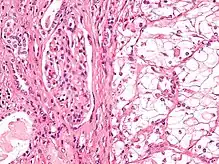

The most common type of kidney malignancy is renal cell carcinoma,[33] which is thought to originate from cells in the proximal convoluted tubule of the nephron.[15][34] Another type of kidney cancer although less common, is transitional cell cancer (TCC) or urothelial carcinoma of the renal pelvis.[35] The renal pelvis is the part of the kidney that collects urine and drains it into a tube called the ureter.[35] The cells that line the renal pelvis are called transitional cells, and are also sometimes called urothelial cells. The transitional/urothelial cells in the renal pelvis are the same type of cells that line the ureter and bladder. For this reason TCC of the renal pelvis is distinct from RCC and is thought to behave more like bladder cancer.[35] Other rare types of kidney cancers that can arise from the urothelial cells of the renal pelvis are squamous cell carcinoma and adenocarcinoma.[15]

- Papillary RCC